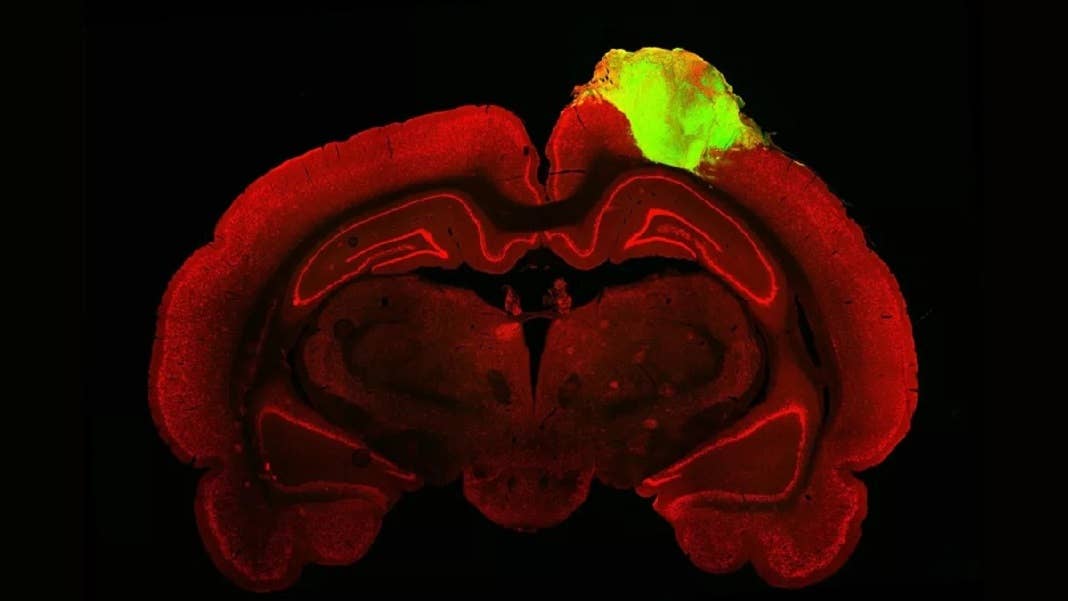

In a first test, the team used a popular tracer to map the connections between the organoid and the animal’s eye. Similar to a dye, the tracer is a virus that hops between neural connections—dubbed synapses—while carrying a protein that glows a bright green under a fluorescent microscope. Like a highlighted route on Google Maps, the light stream clearly connected all the way to the transplanted mini-brain, meaning that its circuitry linked up, through multiple synapses, to the rats’ eyes.

Image Credit: Jgamadze et al.